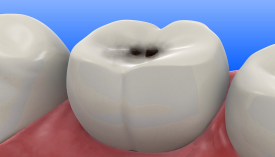

Зуб болит только на сладкое — это уже кариес?

Это не «показалось» и не «пройдёт само». Это сигнал, который зуб подаёт одним из самых ранних способов. И чаще всего этот сигнал — начальный кариес.

- Начальный кариес Боль кратковременная, появляется именно при контакте со сладким. На зубе могут быть:

- белые, желтые или полупрозрачные пятна,

- небольшие шероховатости или углубления,

- участки, где эмаль выглядит «не так, как раньше» («вмятинки»).

Это признак того, что эмаль теряет минералы и начинает разрушаться. Если ничего не делать — кариес будет прогрессировать, появится полость, а боль станет постоянной.

- Пятна, черные точки, вмятинки или маленькие дырочки на зубе. Белые или тёмные участки — признак начавшегося разрушения эмали.